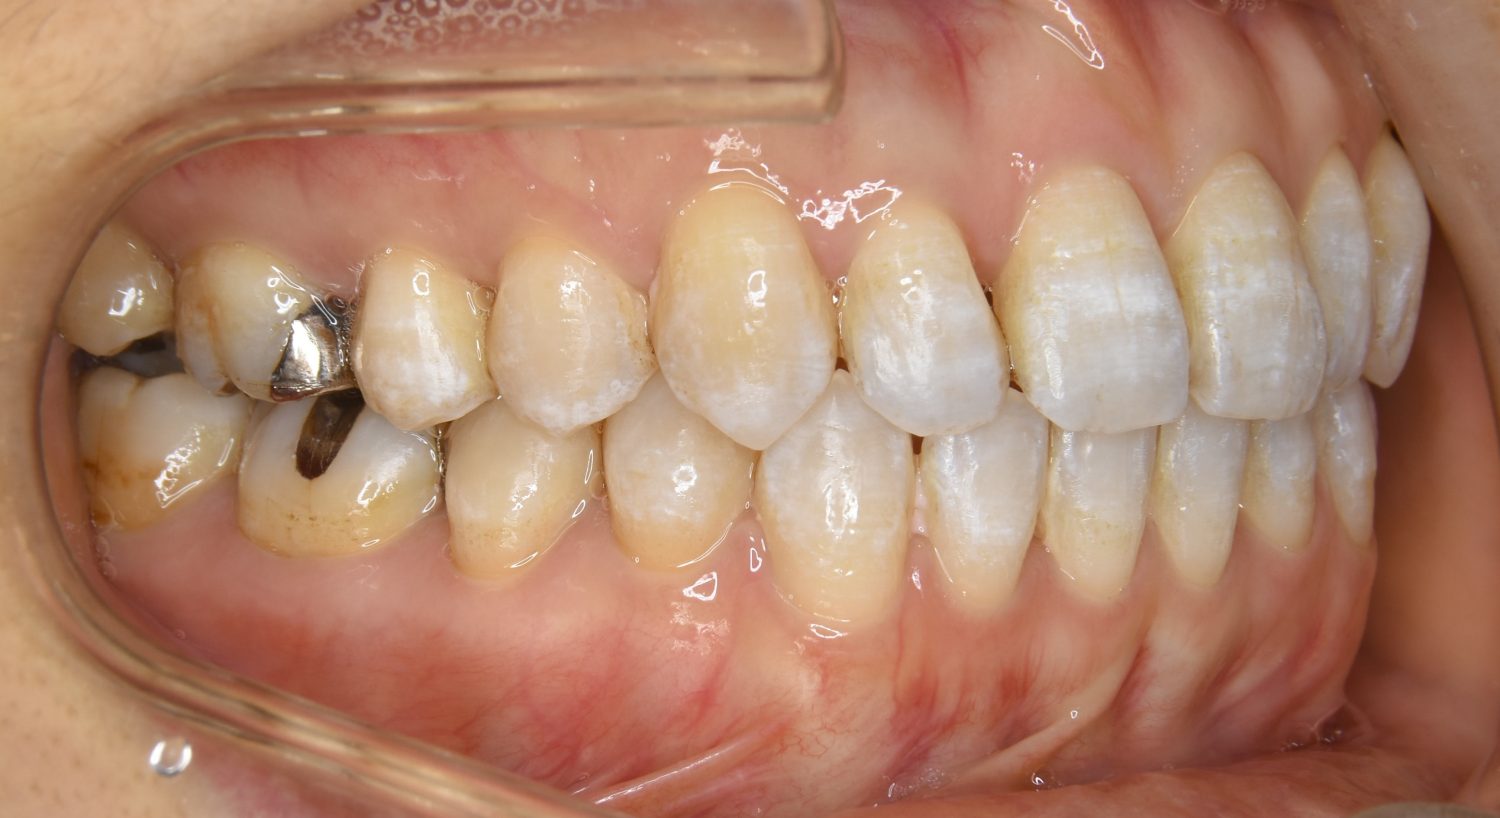

前歯部開咬の症例紹介①

Before

主訴

前歯が開いているのが気になる。

治療内容

上リンガルブラケット(舌側装置)、下ラビアルブラケット(唇側装置)に矯正用アンカースクリューを併用し非抜歯で治療を行いました。

治療費

1,200,000 円(税込)

治療期間

33ヶ月

通院回数

34回

想定されたリスク

※歯根吸収、歯肉退縮、歯髄壊死、顎関節症状

上下の前歯が開いており前歯では全く噛めていない状態でした。臼歯の圧下を行うことで前歯でも咬合できるようになり機能面のみでなく審美面も著しく改善しました。